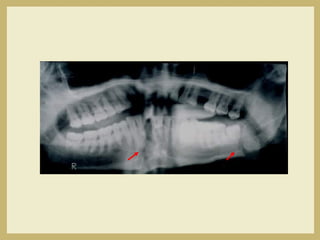

• DIAGNOSTIC IMAGING

– Panorex

Mandibular Fractures

• 50% of mandibular

fractures are multiple

– Examine patient and

radiographs closely and

suspect additional

fractures